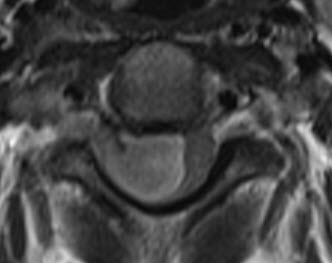

The patient was sent for thorough investigations and MRI cervical spine performed 04-September-2016 showed huge meningioma 33x12.7 mm intradurally pushing the spinal cord to the left. Spectroscopy was typical for meningioma and the mass was lacking fibers. There was and extension to the right C1-2 foramen reaching the vertebral artery pushing it anterior.

In prone position with the use of IOM ISIS, laminectomy of C2-3 and partial of C1 was achieved. The dura was opened slightly right parallel to the midline. The dumbbell-shaped appearance of the tumor was due to right C2 anterior and posterior rootlets, which were constricting the tumor and they were preserved to the end of surgery. The matrix of the meningioma was the right lateral wall of the dura, which was coagulated and piece-meal resection of the tumor was performed. MEP was troubleshooting and not informative. After the resection of the tumor a tiny piece and the emergence of the right C1 was removed trying during that to preserve the rootlets. Using MultiGen, bipolar motor stimulation of right C2 was achieved with 1.0 V. Motor stimulation of the right side of the spinal cord and a brisk response of the right upper and lower limbs was achieved above the tumor resection area. Irrigation of the area with 1 ampoule Papaverine diluted with 20 ml saline. The dura was closed water-tightly. Routine closure of the wound. The patient was sent to MRI before extubation.

Fig-17: Anatomical architecture of the spinal cord at C2-C3 level.

Fig-20: Check MRI before extubation.

Fig-21: Check MRI before extubation,